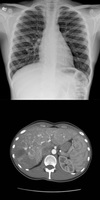

Imaging

CXR: ARDS, exclude perforated DU

AXR: sentinel loop, pancreatic calcification

USS: gallstones and dilated ducts, inflammation

Contrast CT: Balthazar severity score